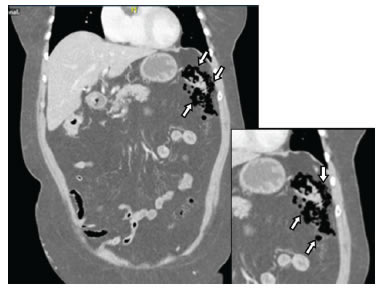

En las tres pacientes, la TC abdominal con contraste mostró el neumoperitoneo pericólico o localizado a menos de 5 cm del asa inflamada sin aire distante (figuras 2 y 3); dos presentaron divertículos en el ángulo esplénico, colon descendente y sigmoide, y una en el colon sigmoide únicamente.

La diverticulitis en las tres pacientes fue de grado Ia por la presencia de inflamación pericólica y la clasificación de Hinchey modificada por Wasvary, y grave por la presencia de aire externo a la luz intestinal en la TC y la clasificación de Ambrosetti (tabla 1) 5.